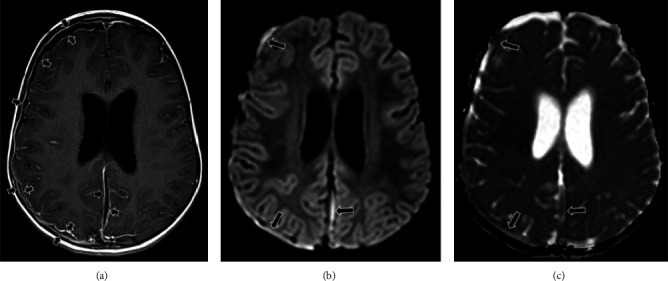

Abstract Image